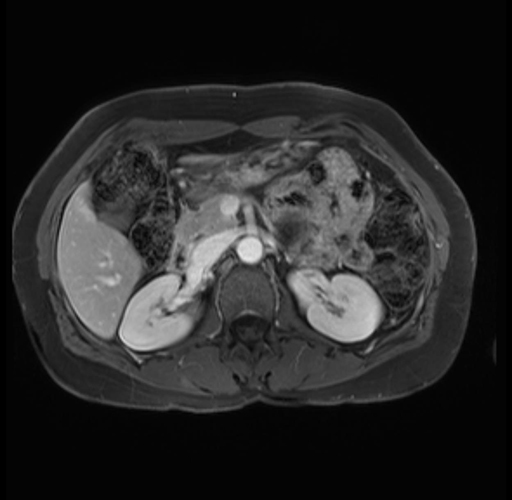

Imaging Analysis

Look through the patient's CT scan to identify any areas of concern for the necessary procedure.

Based on your CT findings, which issue(s) are present and would give reason for "planned slowing down moment(s)" in this case?